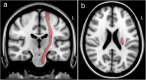

Intracerebral hemorrhage (ICH) prognostication during the acute phase is often subjective among physicians and often affects treatment decisions. The present study explores objective imaging parameters using quantitative corticospinal tract (CST) fiber reconstruction during the acute phase of ICH and correlates these parameters with functional outcome and patient recovery. We prospectively enrolled nonsurgical spontaneous supratentorial ICH patients and obtained an MRI scan on day 5 ± 1. Q-space diffeomorphic reconstruction was performed using DSI Studio, and quantitative anisotropy (QA) was calculated. The CST was reconstructed based on QA. The dichotomized modified Rankin Scale score on day 90 (favorable outcome = 0-2) and Barthel Index (favorable recovery = 100 on day 90 or improvement between discharge and day 90 > 60%) were assessed. Thirty-three patients, median age 72 years (interquartile range (IQR) 64-83), 21 female (64%), 21 (64%) with lobar hemorrhage, median ICH volume on admission 15.0 (IQR 7.0-27.4) mL, were included. Sixteen patients (48%) had a favorable outcome and 24 (73%) had a favorable recovery. The mean number of ipsilesional reconstructed CST fiber pathways was higher in patients with favorable outcomes (153 (standard deviation (SD) 103) vs. 60 (SD 39), p = 0.003) and predicted outcome after adjustment (Exp(B) = 1.016 (95% CI = 1.002-1.030)). QA in the ipsilesional posterior limb of the internal capsule showed a trend towards an association with favorable outcome (Exp(B) = 1.194 (95% CI = 0.991-1.439 (adjusted))). The total (ipsilesional + contralesional) number of reconstructed fiber pathways was associated with favorable recovery (Exp(B) = 1.025 (95% CI = 1.003-1.047 (adjusted))). Quantitative tractography parameters assessed in the acute phase of ICH may represent a promising predictor of long-term outcome and recovery. This might facilitate prognostic evaluation and organization of rehabilitation.